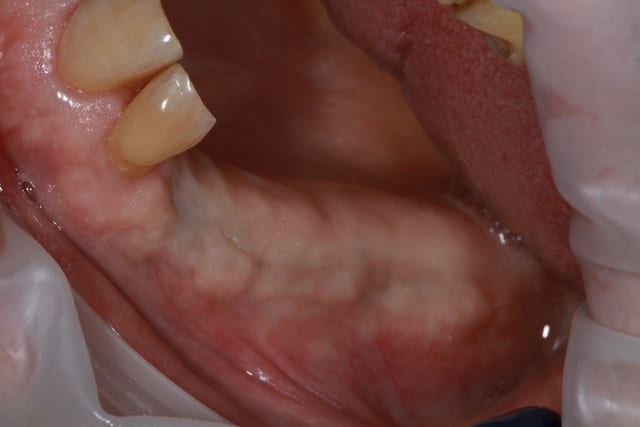

09/10/2013 à 18h33

vue à 8 jours

les photos